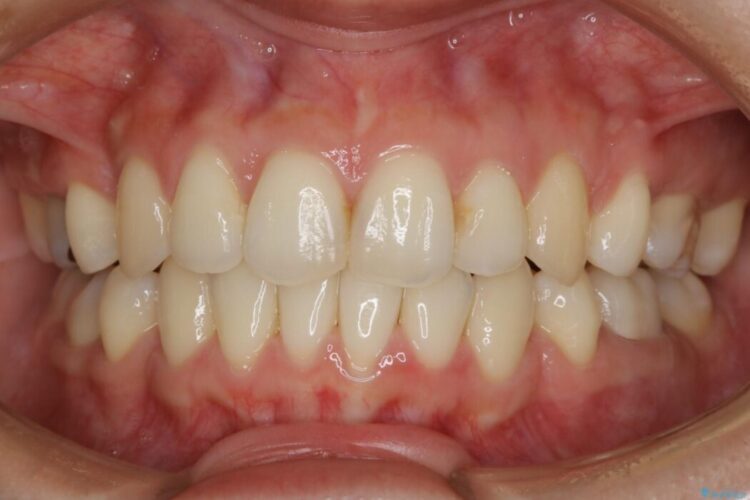

笑った時に見えるガタついていた見栄えが改善されて歯列弓もきれいな形に整い、患者様にはご満足いただけました。